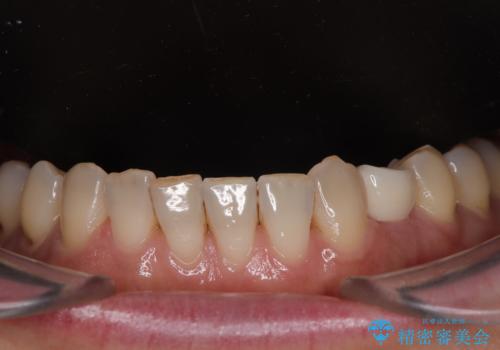

治療は計画通りに進み、約3か月で最終補綴まで完了。

見た目だけでなく、しっかり噛める機能も回復し、患者様にも大変ご満足いただけました。